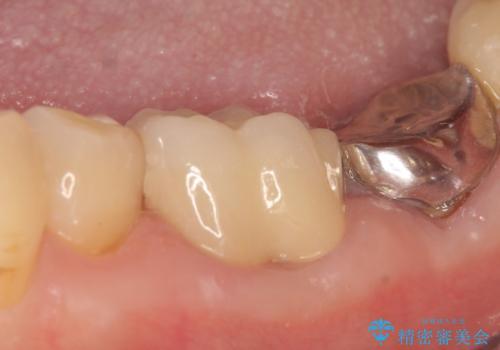

- 保険治療で装着されたかぶせ物と詰め物を変更したいとのことで来院されました。

自然なオールセラミックへ変更することとなりました。

金属を使わないセラミックへ変更することで、自然な見た目になるとともに、ぴったりとした精度の高いかぶせ物を装着することができました。